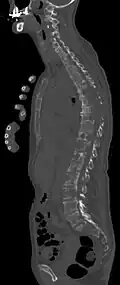

- Comparaison scanner/IRM pour des métastases ostéolytique d'un cancer du sein dans la colonne vertébrale

Scanner sagittal reconstruit, représentation dans la fenêtre osseuse. Comme la patiente avait des métastases dans toutes les régions du corps, elle ne pouvait pas lever les bras pour l'examen, ce pourquoi les mains sont présentées.

Scanner sagittale, parties molles. Outre les métastases dans la colonne vertébrale, qui envahissent en partie le canal médullaire vers l'arrière, métastases aussi dans le sternum. Plus des métastases dans le foie.